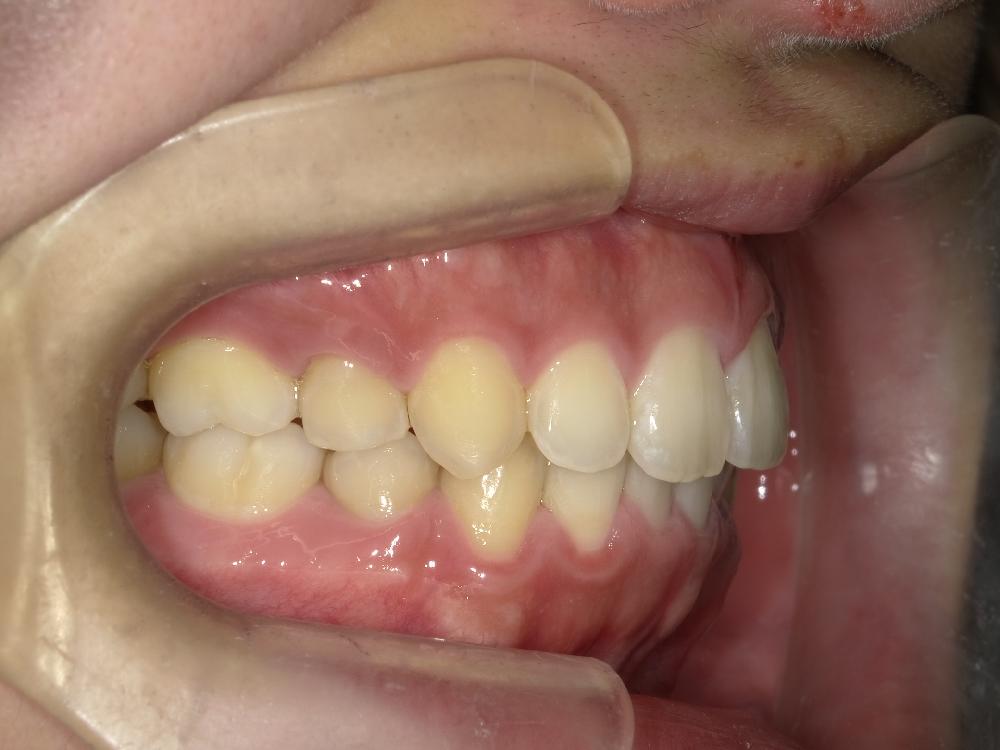

治療前左側

治療前右側